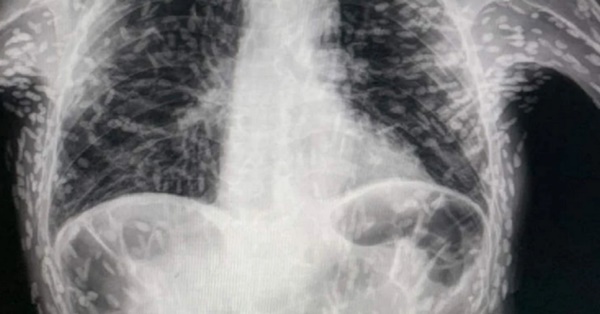

Sau khi được bác sĩ chỉ định chụp X-quang, anh này vô cùng sửng sốt khi thấy khắp người mình có những đốm trắng. Sau đó, bác sĩ giải thích rằng bệnh nhân đã bị nhiễm ấu trùng sán lợn (cysticercosis). Do ăn phải trứng sán dây (có thể do thực phẩm bị nhiễm sán dây).

Thông thường, việc nhiễm ấu trùng sán lợn vô hại vì sán sẽ nhanh chóng chết đi. Tuy nhiên, các u nang - do giun chết để lại - có thể gây ra các vấn đề về sức khỏe.

Nếu u nang bám vào phổi có thể gây ho và đau ngực. U nang trong não hoặc tủy sống có thể dẫn đến tình trạng bệnh ấu trùng sán lợn hệ thần kinh trung ương. Gây động kinh và co giật. Nếu u nang xuất hiện ở mắt sẽ làm rối loạn thị lực và có khả năng gây nhiễm trùng.